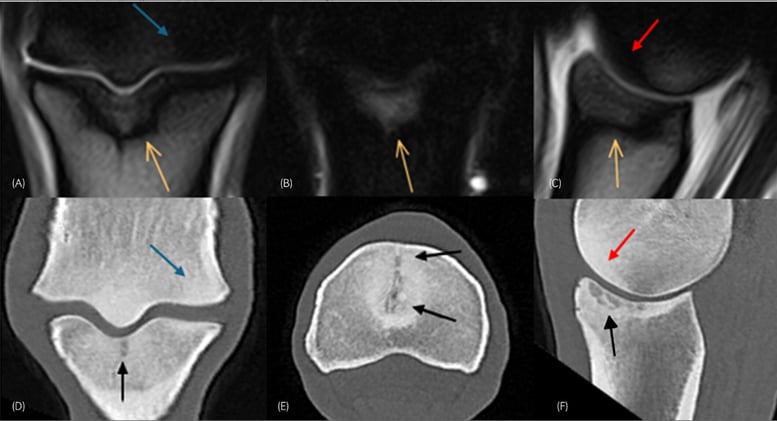

MusculoskeletalMusculoskeletal

+2+2